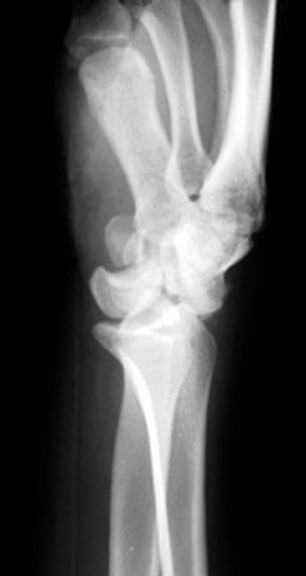

肱骨髁上骨折

肱骨髁间骨折